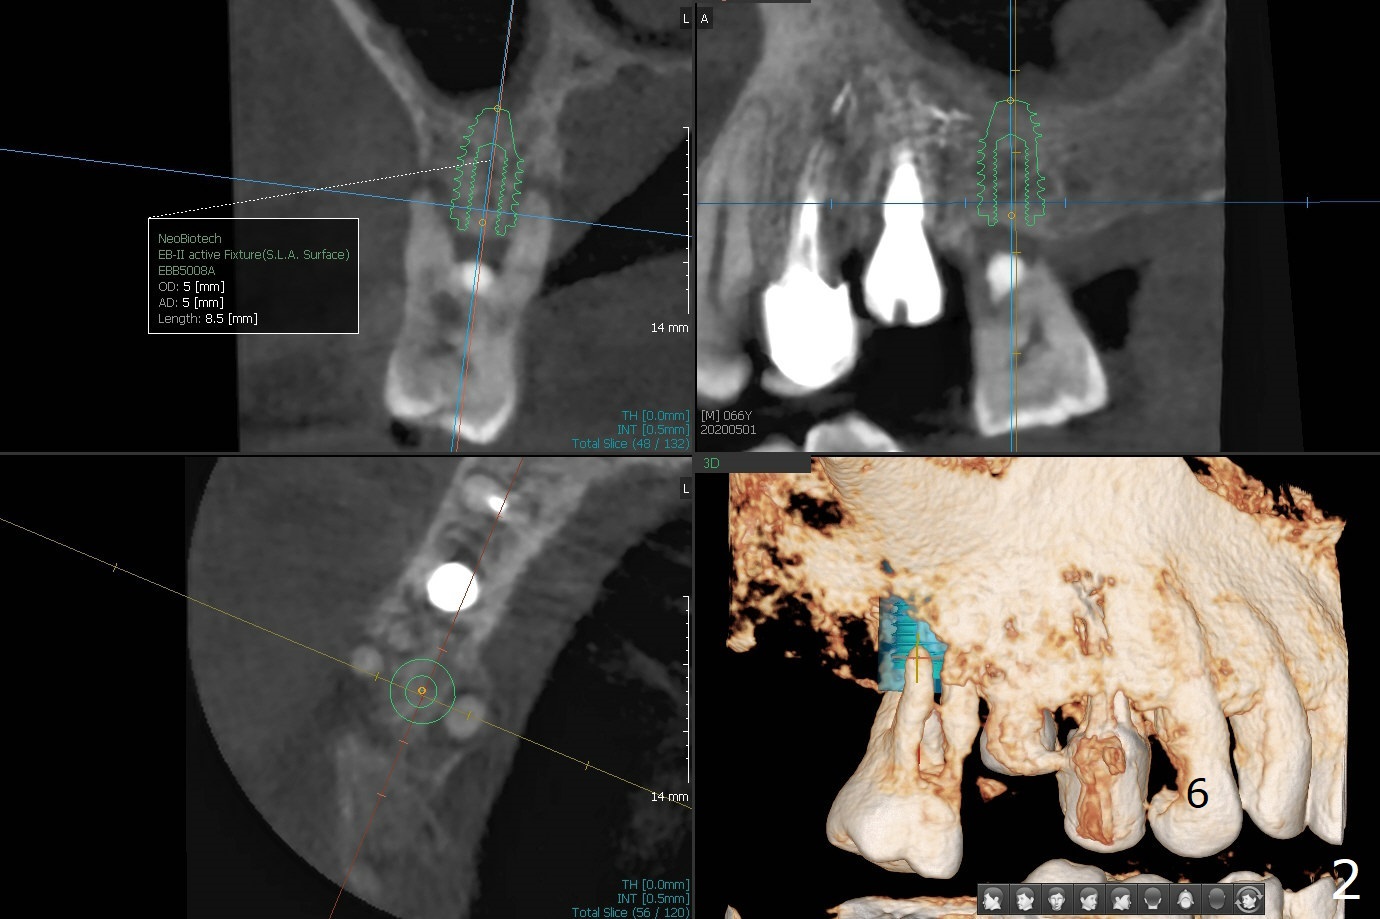

When implants at #4, 13 and 14 are placed, the patient wonders how many more implants are needed. From 0 (considering a lower RPD) to 5 (#3, 19, 20, 25 and 30). The tooth #3 seems to have periodontal-endodontic disease (Fig.1,2). Since the ridge is narrow at #19 and 20 (Fig.3), ridge split at #19 and a 1-piece implant at #20 are planned (Fig.4,5-9). The implant at #19 will be placed in an ideal prosthetic position (Fig.5). The ridge transverse bony cut will be made free hand in the middle (Fig.6,6'), followed by 2 vertical cuts and 1 apical transverse one in the 1st stage of procedure. In order to rotate the buccal block easier (Fig.6 pink curved arrow), the apical transverse cut will be wedge in shape (Fig.6 (red), 6' (double lines), 7 (black)). In the 2nd stage, the ridge top split will be extended by using a chisel (Fig.7 longer red line) and the buccal block will be pushed buccally (Fig.8). A guide will be seated to finish osteotomy (Fig.9 white) and implant placement.